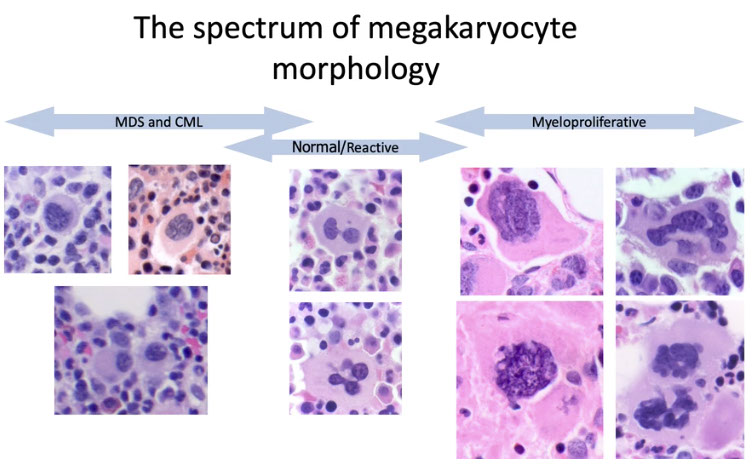

Challenges of diagnosis PMF[2]:

-- close attention to morphology and mutation status (JAK2/MPL/CALR) is helpful

- morphologically distinct from ET; erythrocytosis is absent

-- increased bone marrow cellularity and more frequent, clustered megakaryocytes in early PMF compared to ET

Megakaryocytic hyperplasia and clustering.

-- "Dwarf mgkcs" - lots o small hypolobated megs